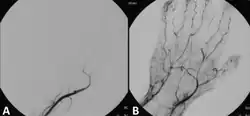

A Doppler evaluation is often the first imaging choice to diagnose ALI because it is inexpensive, accessible, non-invasive, and can be done in a short amount of time.[2] It is used to show the extent and severity of the ischaemia by showing flow in smaller arteries. An occlusion of the artery would be seen by decreased or absent flow distal to the occlusion. Doppler ultrasound can even distinguish between embolic and thrombotic plaque. The former would show a delineated, round thrombus, whereas the latter would show narrowed arterial lumen with atherosclerotic plaque.[2]

Endovascular intervention

Endovascular interventions for ALI are minimally invasive procedures designed to quickly restore blood flow and avoid more extensive surgery. In endovascular interventions, a catheter is used to deliver medication such as thrombolytics to dissolve the clot. In the past, streptokinase was the main thrombolytic chemical. More recently, drugs such as tissue plasminogen activator, urokinase, and anistreplase have been used in their place. Mechanical methods of injecting the thrombolytic compounds have improved with the introduction of pulsed spray catheters—which allow for a greater opportunity for patients to avoid surgery.[21][22] Pharmacological thrombolysis requires a catheter to be inserted into the affected area, attached to the catheter is often a wire with holes to allow for a wider dispersal area of the thrombolytic agent. These agents lyse the ischemia-causing thrombus quickly and effectively.[23] However, the efficacy of thrombolytic treatment is limited by hemorrhagic complications. Plasma fibrinogen level has been proposed as a predictor of these hemorrhagic complications. However, based on a systematic review of the available literature until January 2016, the predictive value of plasma is unproven.[24] After the clot has been dissolved or removed, a stent or balloon may be placed to keep the artery open and prevent further ischemia.